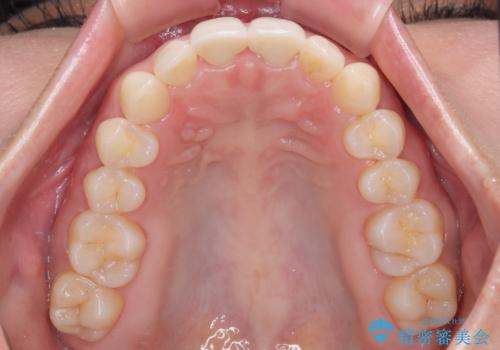

- 保険診療で装着した前歯の色調と厚みを気にして来院された患者様です。

黄ばみや厚みが改善され、まるで本物の歯のように調和した口元となりました。